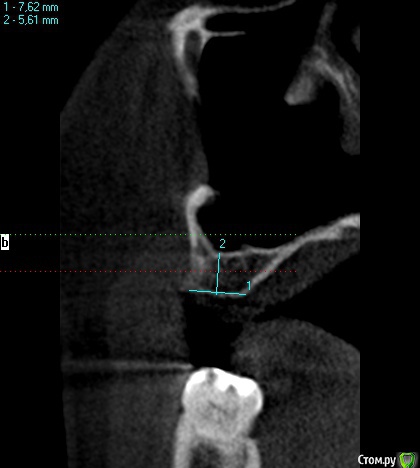

wladdX Опубликовано 27 февраля, 2019 Поделиться Опубликовано 27 февраля, 2019 (изменено) Скриншоты Сколько успел Изменено 27 февраля, 2019 пользователем wladdX Ссылка на комментарий

red_butler Опубликовано 27 февраля, 2019 Поделиться Опубликовано 27 февраля, 2019 соустье нужно посмотреть, но предварительно - не вижу препятствий для проведения открытого синуслифта Ссылка на комментарий

kramer Опубликовано 27 февраля, 2019 Поделиться Опубликовано 27 февраля, 2019 Закрытый синус-лифт + 10 мм имплантат Ссылка на комментарий

red_butler Опубликовано 27 февраля, 2019 Поделиться Опубликовано 27 февраля, 2019 8 мм имплант и закрытый синус без графта Ссылка на комментарий

колесников Опубликовано 3 марта, 2019 Поделиться Опубликовано 3 марта, 2019 У вас речь идёт об одном импланты в области 16. Одиночный короткий Имплант не рекомендуется ни одним из производителей имплантов. Открытый синуслифтинг не показан из за особенностей строения пазухи в этой области,показан закрытый. Так же рекомендовал бы Астра тек,4.5х9. А также:дистализация 17го и имплантация в области 47.. либо удаление 17го,имплантация 17,16,47 Ссылка на комментарий